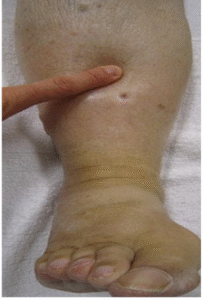

• Shape of the limb: The proximal part of both limbs was huge compared to the distal part (distorted appearance, the right was more so)

• Skin folds and creases: present in the proximal part of the limb.

• Type of swelling/oedema: minimal pitting in the distal leg

• Subcutaneous tissue changes: rubbery/fatty

• Skin condition: tissue thickened like fibrosis (no bump and no ulceration) in the distal leg.

Also, lymphedema is characterised by distal swelling of extremities. But she has more proximal enlargement than distal, skin is more of a rubbery texture, not leathery, directing us away from lymphedema.

• It was a gradual onset and bilateral involvement

• The swelling stops at the ankle and wrist

• Subcutaneous fat deposition

• The presence of spider veins and a fold of fat

• Discolouration and edema of the distal leg

• Fibrosis-like tissue thickening